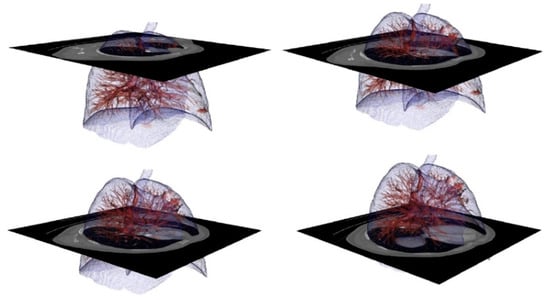

3.2. Results Visualization

2.5. 3D Visualization Platforms

- A tool is offered to physicians to visualize medical images in 3D with three different versions: augmented, virtual reality, and computer.